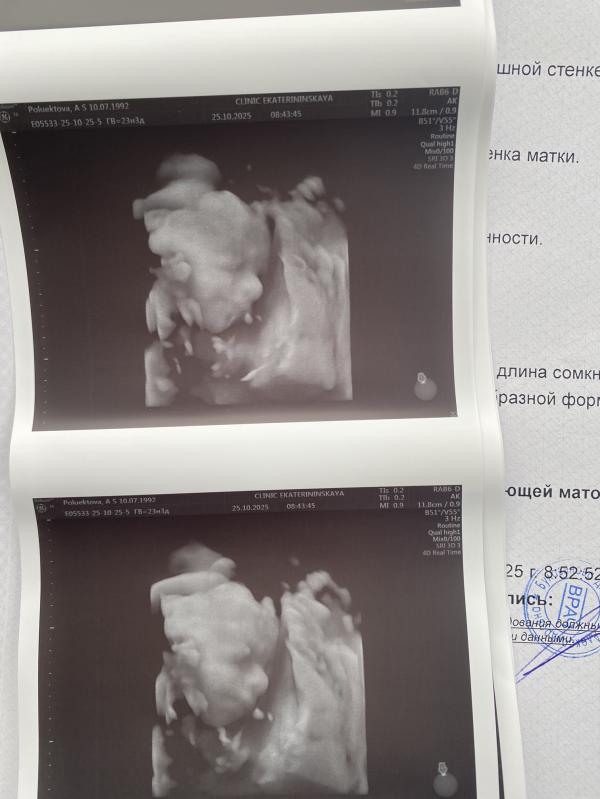

На выходных сделали 3д узи- дочь копия папа 😂